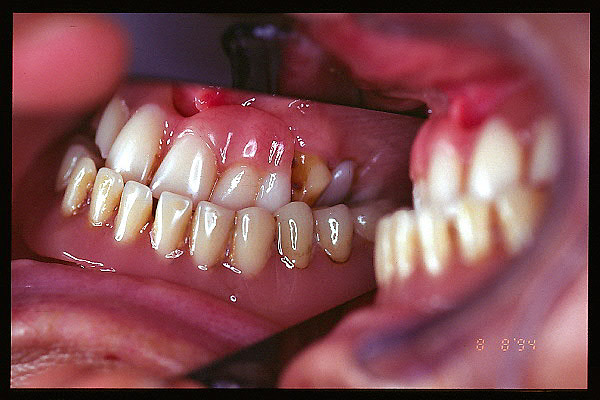

CM Desgaste por bruxismo, presencia de cálculo